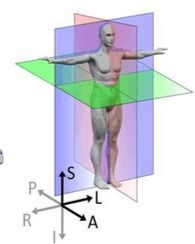

R-A-L-P-I-S" 是描述人体方位(解剖学方向)的一组首字母缩写,用于在医学影像(如 CT、MRI)或解剖学中精确标注身体的不同方向。每个字母代表一个方向:

R – Right(右)

A – Anterior(前)

L – Left(左)

P – Posterior(后)

I – Inferior(下)

S – Superior(上)

由此我们可以根据医学图像可视化软件ITK-SNAP中的标识识别每个窗口指向的切面